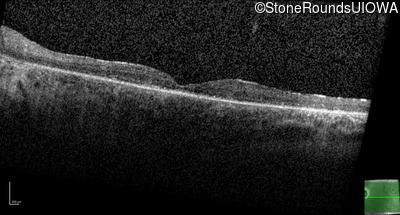

Optical Coherence Tomography - Left - 20/50

Exemplar / OCT Stack

OCT Stack